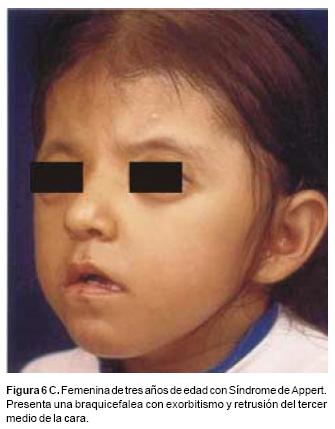

También los controles radiológicos durante el proceso de distracción mostraron que no se produjo la creación de espacios muertos intracraneanos durante los avances. En todos los pacientes con sinostosis bicoronal el avance frontoorbitario produjo excelentes resultados estéticos dando una nueva forma a la región frontal y proyectando mejor el reborde supraorbitario. En los niños con enfermedad de Crouzon y síndrome de Apert, se corrigió en forma muy satisfactoria el exorbitismo al resolver las graves exposiciones corneales (Figuras 5 A, B, C, D, E, F, G, H), en los que se utilizó el avance simultáneo del tercio medio, este cambio óseo corrigió muy satisfactoriamente la retrusión del mismo, ampliando la vía aérea y resolviendo en muchos casos grandes problemas ventilatorios durante el sueño (Figuras 6 A, B, C, D, E, F). Los pacientes con plagiocefalia corrigieron significativamente la deformidad frontoorbitaria y los tejidos blandos suprayacentes se adaptaron a la nueva estructura ósea. La clásica órbita de arlequín de estos niños producida por la sinostosis del frontal con el esfenoides, inmediatamente se ve corregida en su forma y su configuración se hace muy similar con la órbita contralateral (Figura 7)(Fig. 7a, 7b, 7c, 7d, 7e, 7f, 7g) (Cuadro II).